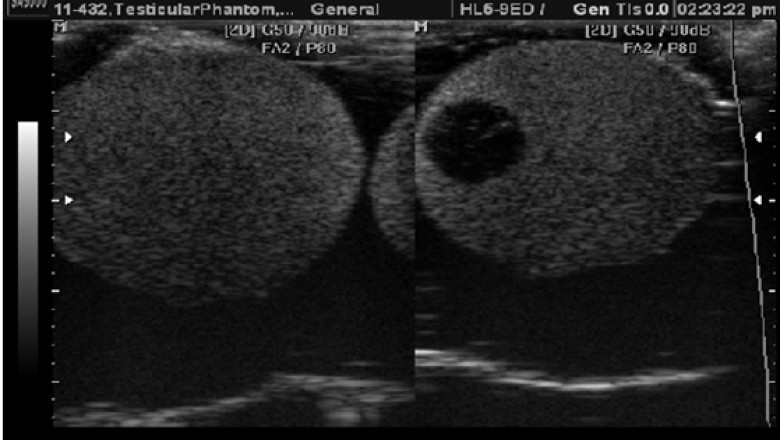

Scrotum ultrasound is an outpatient procedure used to assess the cause of pain or swelling in the scrotum. It’s also sometimes used to guide a biopsy, which is a procedure to remove tissue for further testing. Scrotal ultrasound may be used to diagnose conditions such as hydrocele, varicocele, epididymitis, or testicular torsion.

Scrotal ultrasound is usually performed using a handheld transducer that’s placed against the skin of the scrotum. The transducer emits sound waves that produce images of the inside of the scrotum on a monitor.